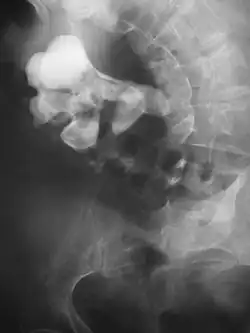

Where a CT scan is unavailable, an intravenous pyelogram may be performed to help confirm the diagnosis of urolithiasis. This involves intravenous injection of a contrast agent followed by a KUB film. Uroliths present in the kidneys, ureters, or bladder may be better defined by the use of this contrast agent. Stones can also be detected by a retrograde pyelogram, where a similar contrast agent is injected directly into the distal ostium of the ureter (where the ureter terminates as it enters the bladder).[61]

Bilateral kidney stones can be seen on this KUB radiograph. There are phleboliths in the pelvis, which can be misinterpreted as bladder stones. -